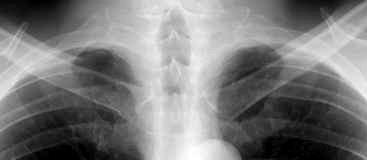

Síndrome de afectación postcardiaca (postcardiac injury)

Post infarto 1-7 % (Dressler)

Trauma cerrado Implantación marcapasos

Cirugía cardiaca. 17-31% (Post.pericardiotomía)

3707 pacientes 29 Derrames (0,78%) > de 25% del hemitórax

Todas menos 2 Izdos.

Angioplastia

By-pass coronario 21-10-03